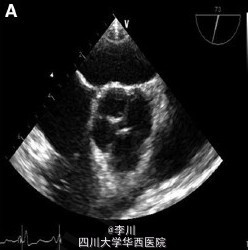

患者,女,35 岁,因车祸入院,既往曾行直肠阴道瘘修补术,诉劳力性呼吸困难多年。面部特征表现为双侧耳前凹陷、脸部不对称。查体提示左侧第二肋间舒张期杂音。血常规、心电图、胸片均未见异常。

结合病史辅助检查、体格检查,诊断为猫眼综合症,予以行主动脉瓣机械瓣置换术治疗。

猫眼综合症是罕见的常染色体异常,核酸排列为 22q11.1q11.21,22 号染色体长臂三体,额外的染色体来源于 22 号染色体近段, 并且带有 2 个染色体的着丝点和双卫星区域。其因有虹膜缺损似猫眼而得名,常表现为眼球异常、缺陷。其他特征包括肛门闭锁、外耳及肾脏心脏多发畸形,临床表现各异。心脏缺陷常表现为肺动脉回流异常和法洛四联症。四叶式主动脉瓣诊断主要依靠超声心动图。该病例中观察到四叶式主动脉瓣及中度升主动脉扩张,冠状动脉无异常。因患者有明显的重度主动脉反流症状,行机械瓣置换术治疗。尽管该患者有罕见的腔静脉连接异常,但其没有血流动力动力学异常,故术中未纠正。患者术后瓣膜功能正常。Circulation 2015.4.10 DOI:10.1161/CIRCULATIONAHA.114.013290.